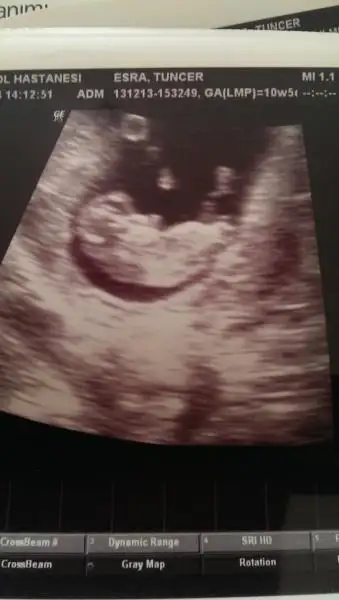

Kizmi desem ama cok kucuk degusedebilir simdilik bi cadi diger koyan arkadas senjn bebe arkasini donmus okla gosterdigin yer dötu gorunmuyorEki Görüntüle 944119 Eki Görüntüle 944121

Rabbim inşAllah kısmet etsin cümlemize. Buarada Nubu tam karşıya bakıyor canım ,birde bir arkadaştan öğrendiğime göre rahim duvarını tam doldurmuş buna görede kız

Kac haftslik daha kucuk gibi annesi ben erkk gibi diyorum ama daha buyumesi lazim tamammi kiz nubu goremedigim icin erjek gibi dedimEki Görüntüle 944853 bizede baka bilirmisiniz acaba benim bebişim